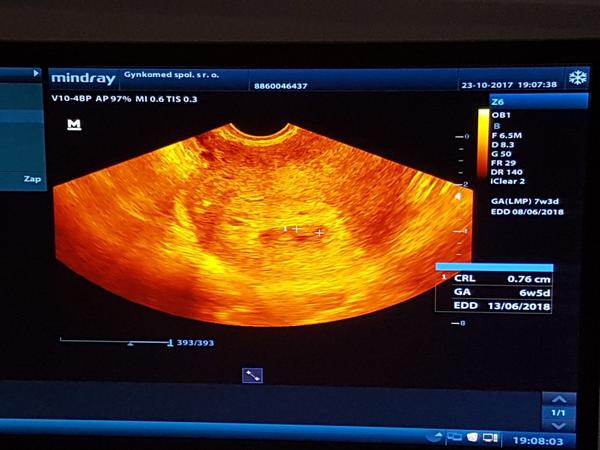

@pisulka27 ja som bola uz na troch sonach, lebo krvacam. Raz za tyzden. Prv krát keď som bola a bolo to o 5 dni menšie, nevedel povedať či to pred 5 dňami sa prestalo vyvíjať, alebo je len 5 dni pozadu. To bol ťažký tyzden. Odvtedy rastie na milimeter presne. Sme proste o 5 dni menší. Zrejme sa uhniezdilo neskôr. Lebo viem presne kedy som mala ovulaciu... neboj, určite je všetko Ok, kedže bije srdiečko.